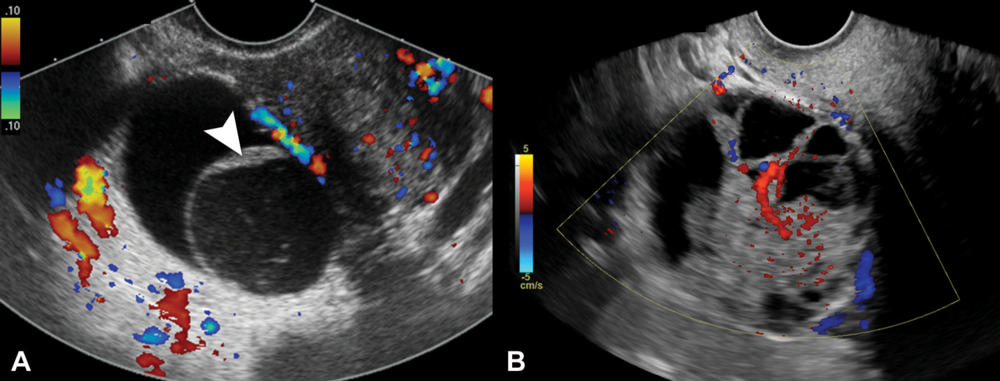

Figure 2. Representative transvaginal US images of nonclassic lesions; color Doppler blood flow with color bar signifies direction of flow. (A) Transverse color Doppler image of right adnexa depicts a multilocular cystic lesion with smooth septation (arrowhead) and no Doppler flow, compatible with a nonclassic lesion without blood flow. (B) Transverse color Doppler image of right adnexa depicts a multilocular cystic lesion with solid component and internal Doppler flow, compatible with a nonclassic lesion with blood flow.